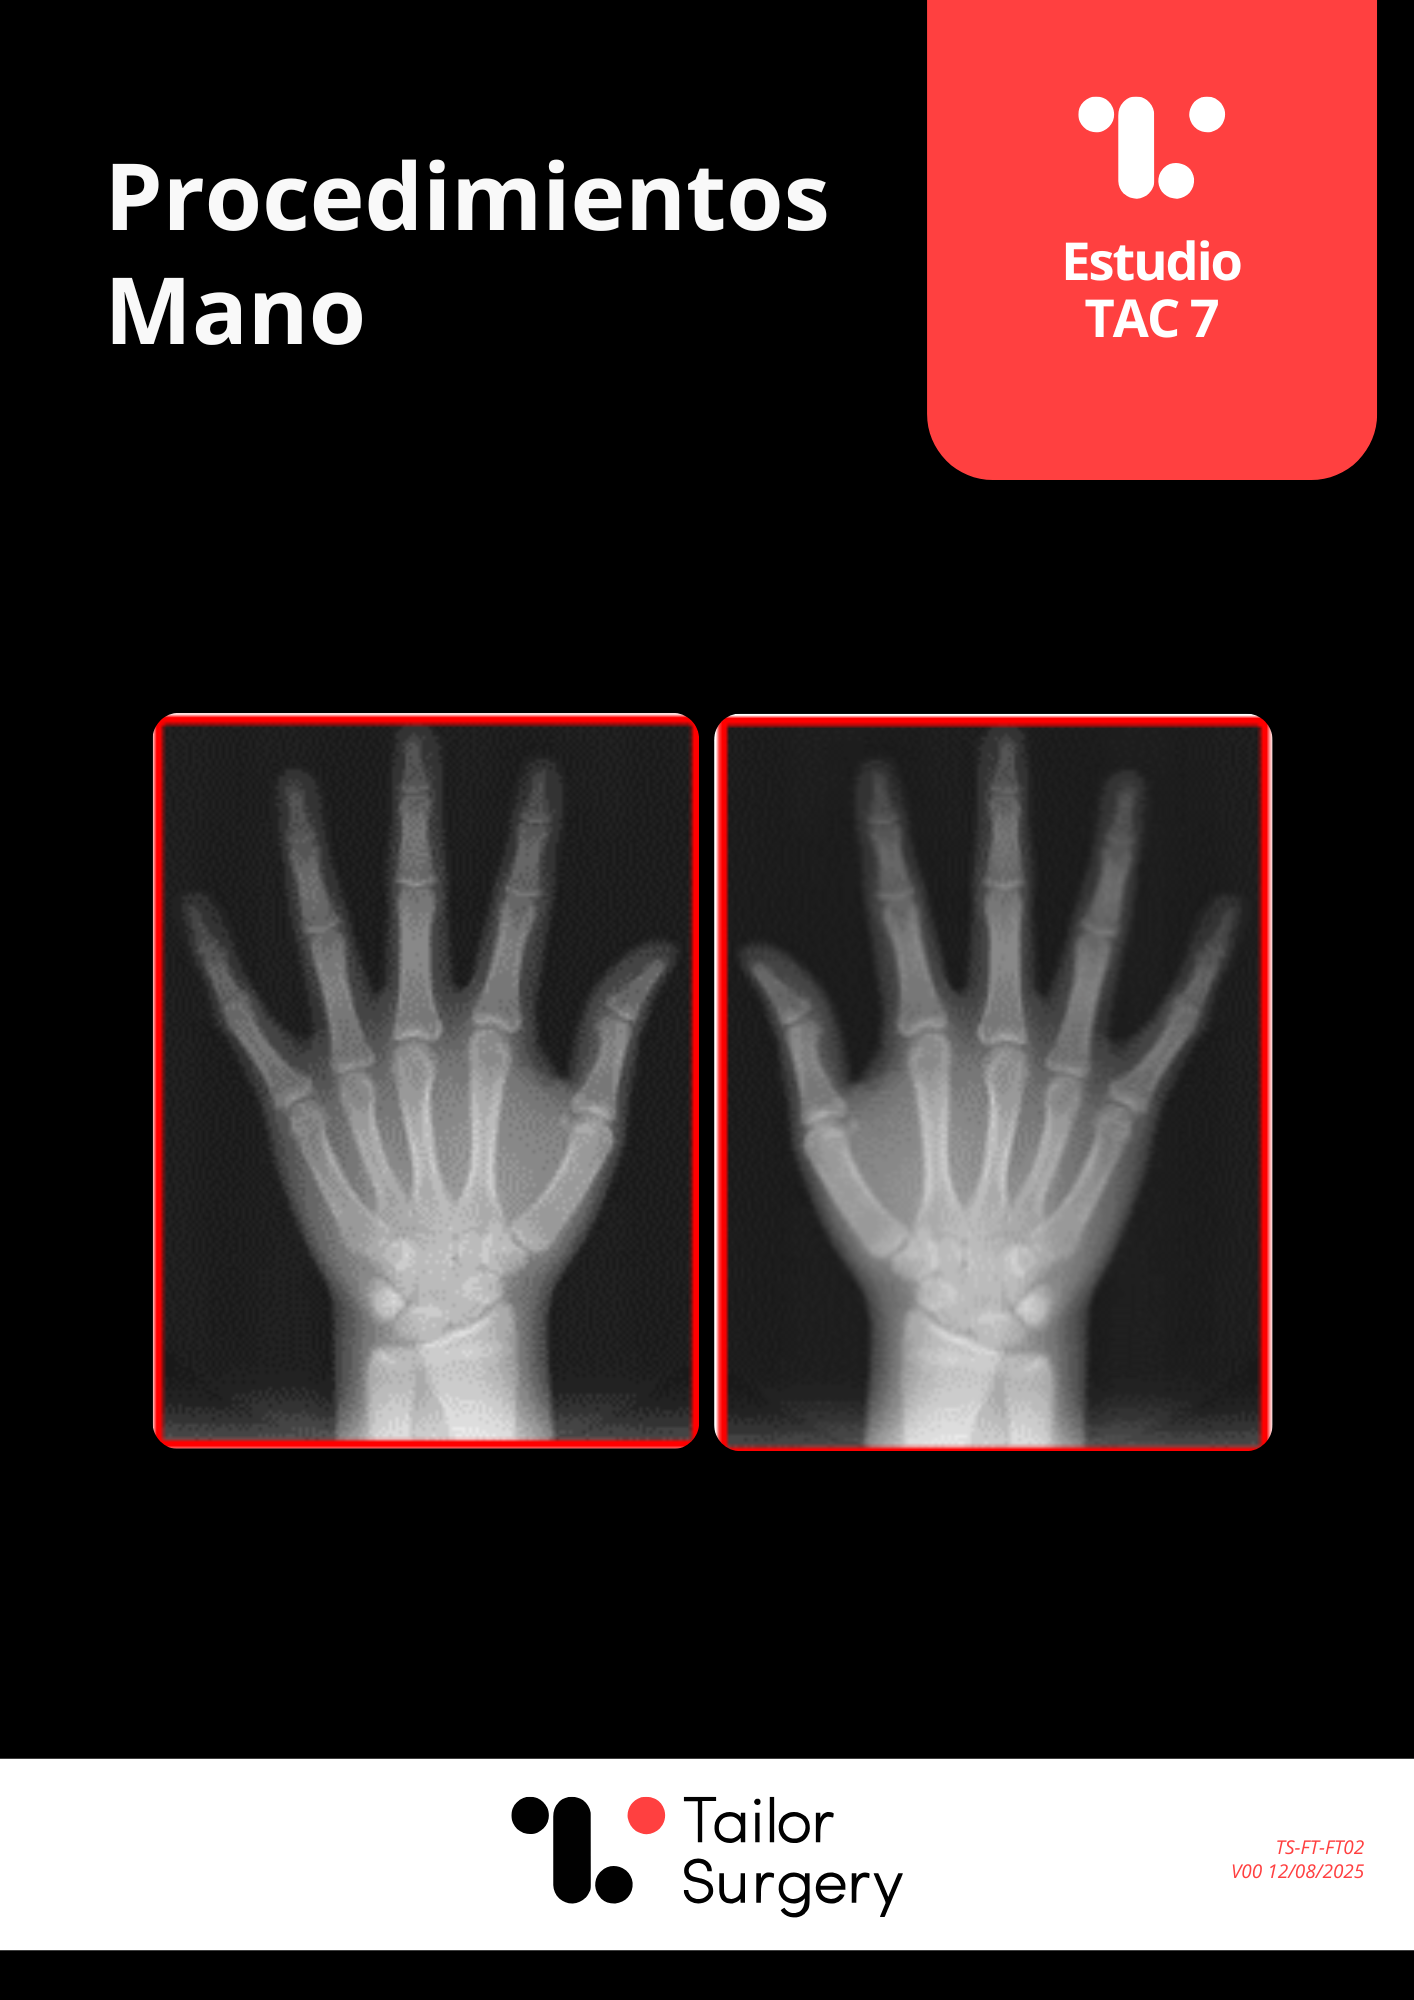

Extremidad Inferior

(baja radiación)

Este documento define el protocolo alternativo de baja radiación para los siguientes procedimientos: • Osteotomía de Tibia Proximal • Osteotomía de Femur Distal • Reconstrucción Ligamentaria Rodilla